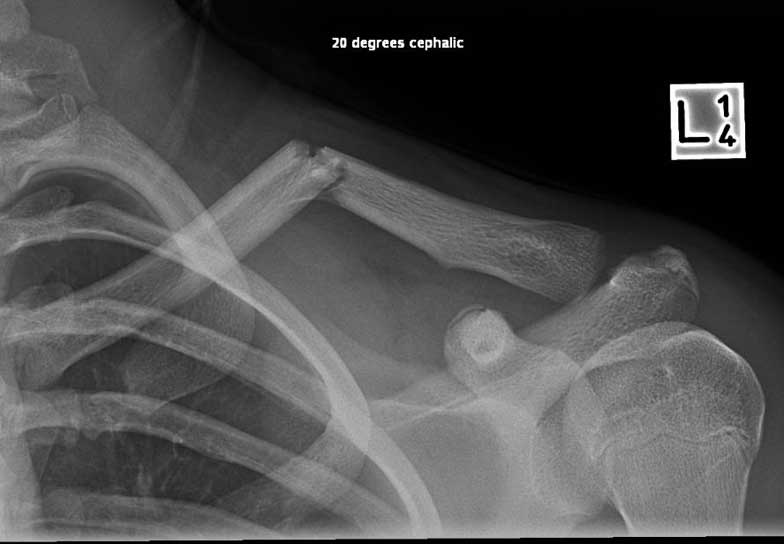

What do Distal Clavicle Fractures Look Like on X-ray and CT?

X-RAY

Click an image to enlarge